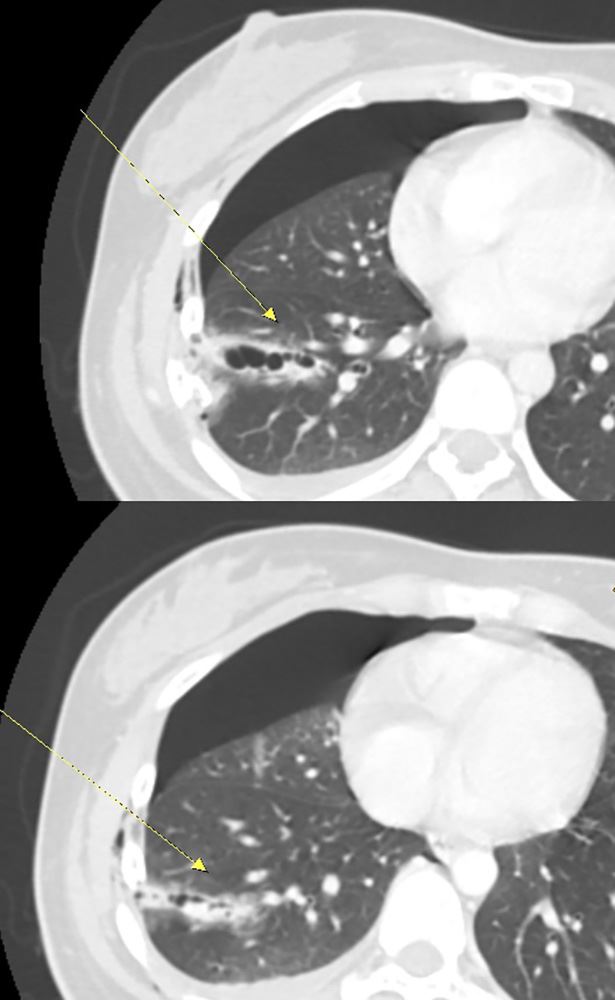

杜承哲表示,胸腔損傷最怕的就是「溫水煮青蛙」,外觀看似只有瘀青,內部卻在持續出血。該患者經電腦斷層掃描,影像證實右側第5至7肋骨骨折,其中兩節肋骨明顯插入肺組織,造成肺臟破裂,且胸腔內積血持續增加,嚴重壓迫肺部擴張。單純引流恐無法止住出血,且無法解決肋骨不穩定的劇痛,若不緊急處理,患者隨時可能因呼吸衰竭或休克而危及生命。